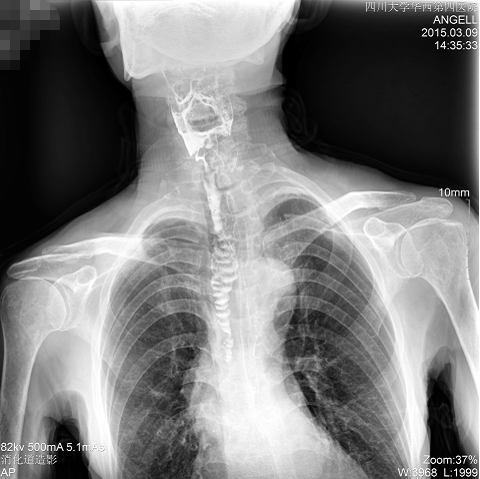

如下圖所示:該患者因吞咽時感到很難受,進(jìn)食時也經(jīng)常咳嗽故就醫(yī)診斷。使用多功能dr為病人進(jìn)行消化道造影診斷,要求他吞鋇后發(fā)現(xiàn),食道各段通過順利,形態(tài)規(guī)則,雙側(cè)梨狀窩不對稱左側(cè)稍淺,多次吞咽動作后,仍見鋇劑滯留,并見鋇劑進(jìn)入氣管,屬于會厭征陽性。會厭功能紊亂,鋇劑進(jìn)入了氣管。

多功能dr斜位影像圖

圖為斜位:通過動態(tài)影像可以清楚看到鋇劑進(jìn)入了支氣管道